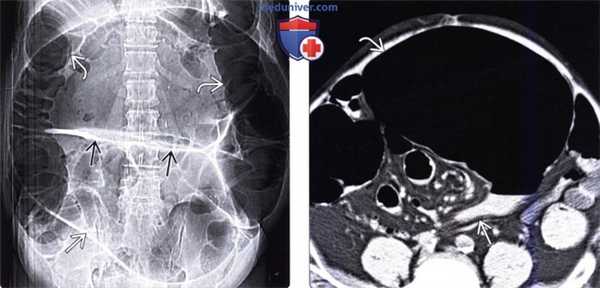

(Слева) На рисунке показано скручивание (заворот) В восходящей ободочной кишки, что привело к обструкции просвета и нарушению кровообращения. Слепая кишка В расширена и вместе с брыжейкой смещена влево и кверху.

(Справа) На рентгенограмме в положении пациента лежа на спине визуализируется растянутая газом слепая кишка, находящаяся по центру живота. Основание слепой кишки направлено кверху, а илеоцекальный клапан направлен в латеральную сторону. Тонкая кишка растянута с наличием газа, в то время как левая половина ободочной кишки находится в относительно спавшемся состоянии.

(Слева) На аксиальной КТ у этого же пациента определяется выраженное растяжение слепой кишки и симптом «водоворота» со стороны илеоцекальной брыжейки в нижних отделах живота справа.

(Справа) На корональной КТ в этом же случае визуализируется в значительной степени расширенная слепая кишка, расположенная по средней линии В. Слепая кишка развернута книзу и кзади, в то время как илеоцекальный клапан В направлен латерально. КТ с реформацией в корональной плоскости является наиболее достоверным методом диагностики, позволяющим обнаружить характерные признаки заворота слепой кишки.

(Справа) На рентгенограмме в положении пациента лежа на спине визуализируется растянутая газом слепая кишка, находящаяся по центру живота. Основание слепой кишки направлено кверху, а илеоцекальный клапан направлен в латеральную сторону. Тонкая кишка растянута с наличием газа, в то время как левая половина ободочной кишки находится в относительно спавшемся состоянии. (Слева) На аксиальной КТ у этого же пациента определяется выраженное растяжение слепой кишки и симптом «водоворота» со стороны илеоцекальной брыжейки в нижних отделах живота справа.